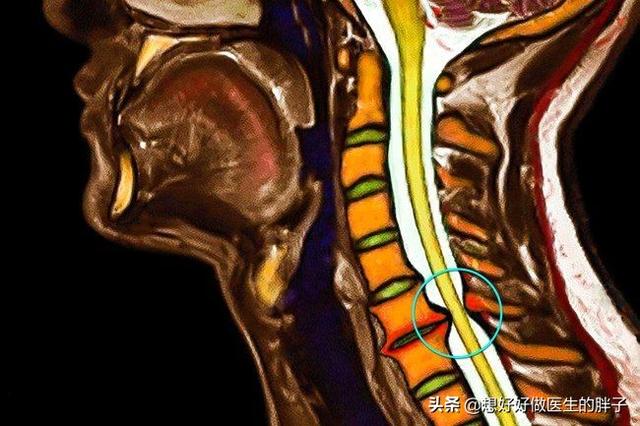

●无论症状的轻重我们都要进行颈椎x线以及核磁的检查,明确到底颈椎间盘突出到了什么样的程度。尤其是那种出现上肢麻木的患者,我们要通过核磁检查明确椎间盘突出到底是中央型的还是周围型的,这决定患者是否可以进行颈椎的牵引治疗。

而x线检查可以明确颈椎椎体是否有严重的骨质增生,曲度是否有改变,对于某一些严重骨质增生的颈椎病患者,还建议患者进行三维ct检查,明确椎管内是否有明显的后纵韧带钙化,下图白色的高亮区域就是钙化的韧带,这么长,这么严重的钙化,患者的神经肯定会受到压迫。